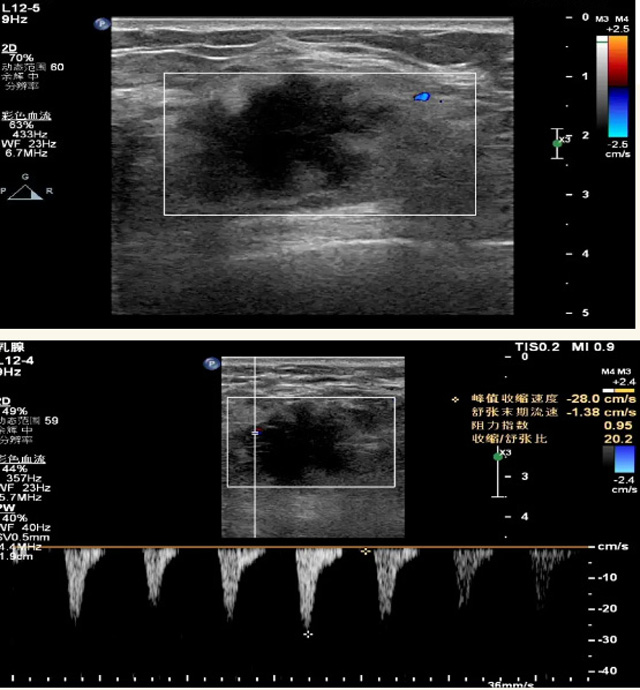

乳腺B超磁共振MRI對(duì)乳腺的檢查效果怎樣?

乳腺B超檢查無(wú)輻射,對(duì)囊性病變敏感,可以實(shí)時(shí)觀察病灶。超聲引導(dǎo)活檢跟手術(shù)前的定位。就是它對(duì)于微小的鈣化查出率比鉬靶稍微差點(diǎn)。磁共振MRI檢查也是是沒(méi)有輻射的,對(duì)備孕跟已經(jīng)懷孕的人士比較友好。不用擔(dān)心這個(gè)輻射影響胎兒?jiǎn)栴}。對(duì)乳腺病灶敏感性較高,致密乳腺病灶、乳腺癌的復(fù)發(fā),準(zhǔn)確鑒別囊性及實(shí)性病變。可以幫助臨床醫(yī)生判斷惡性、良性病變。但是MRI磁共振對(duì)微小鈣化不明顯,微鈣化還是鉬靶靠譜點(diǎn)。檢查時(shí)間比較長(zhǎng),有偽影的影響。費(fèi)用相對(duì)B超,鉬靶高很多。